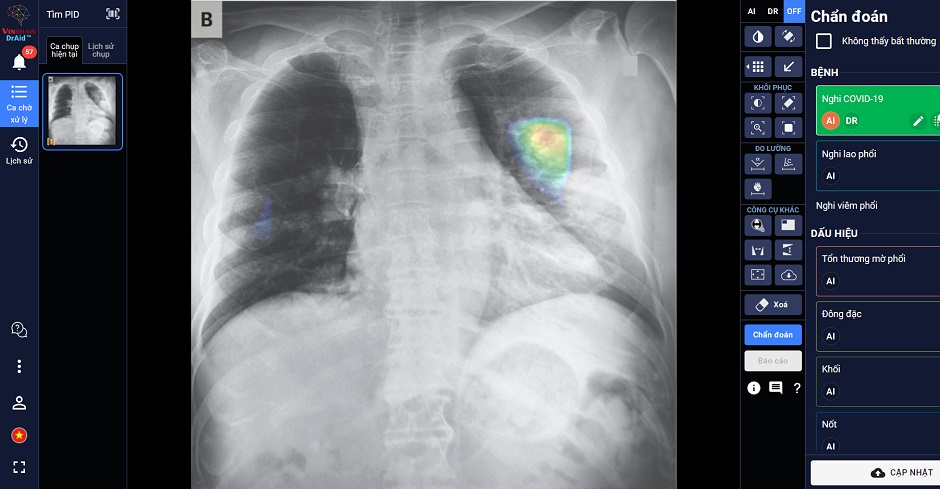

“DrAid for Radiology”– AI Trợ lý Bác sĩ cho Chẩn đoán hình ảnh y tế là sản phẩm đầu tay của VinBrain và cũng là sản phẩm AI hoàn chỉnh đầu tiên của y tế Việt Nam ra mắt phiên bản đầu tiên vào ngày 14/06/2020. Sản phẩm có khả năng phát hiện, sàng lọc trên 21 dấu hiệu bất thường và bệnh lý về Phổi – Tim – Xương trong vòng 5 giây với độ chính xác trên 89%; đồng thời có thể chia sẻ kết quả chẩn đoán thông qua QR code hoặc đường link. Đặc biệt, sản phẩm có khả năng tự cảnh báo COVID-19, kể cả các trường hợp không có triệu chứng hoặc tổn thương phổi nhẹ dựa trên X-quang ngực thẳng, kết hợp cùng xét nghiệm PCR giúp nâng cao độ chính xác, giảm thiểu tình trạng âm tính giả... DrAid cũng nổi bật với tính năng “Hỏi ý kiến Bác sĩ thứ 2 (từ xa)”. Thông qua việc chia sẻ hình ảnh trực tiếp từ DrAid, bác sỹ có thể hội chẩn từ xa với đồng nghiệp hoặc tham khảo ý kiến của các chuyên gia đầu ngành mà không bị ảnh hưởng bởi rào cản địa lý.

DrAid được Ban giám khảo ACM SIGAI đánh giá cao vì sản phẩm đã kết hợp và ứng dụng những kỹ thuật tiên tiến nhất trong lĩnh vực trí tuệ nhân tạo như phân loại nhiều lớp, suy luận theo cấu trúc cục bộ đến tổng quan, học chủ động, đào tạo đối nghịch, mạng nơ ron tích chập phức hợp, nhận dạng giọng nói cho chỉnh sửa báo cáo Y tế tự động, khoanh vùng tổn thương trên ảnh Y tế với kiến thức máy học sử dụng công nghệ cao AI dựa trên mô hình với hàng trăm triệu tham số điểm ảnh (pixel) và dữ liệu lớn hàng triệu ảnh với mỗi ảnh có hàng triệu điểm ảnh (pixel), cùng nhiều kỹ thuật khác tạo nên một dịch vụ trí tuệ nhân tạo phục vụ Y tế toàn diện.